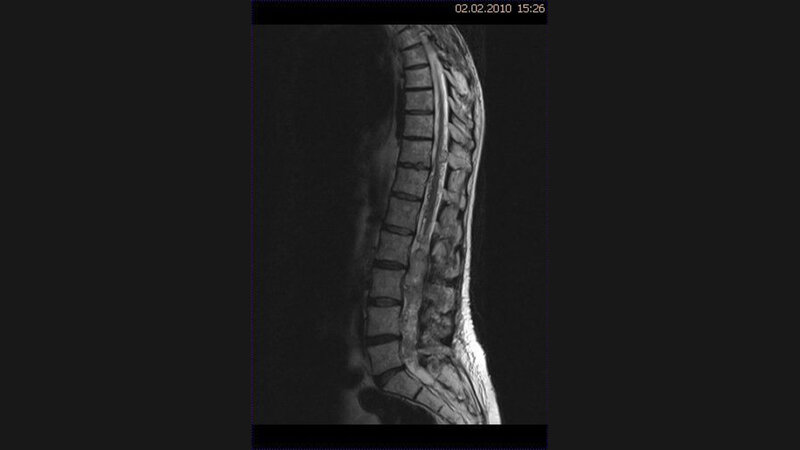

Tumoren des Spinalkanals und des Rückenmarks können erhebliche neurologische Probleme mit Parästhesien, sensomotorischen Defiziten sowie Darm- und Harnblasenstörungen verursachen und auch zur Letalität führen.

Intramedulläre Tumoren sind seltener als demyelinisierende Rückenmarkprozesse. Das MR-Bild der mangioblastome hängt von der Größe ab. Von Hämangioblastomen verursachte Blutungen in den Subarachnoidalraum oder das Hirngewebe sind sehr selten. In der KHBW-Region können zahlreiche Läsionen lokalisiert sein.